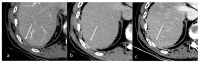

Dual-energy computed tomography (DECT) is one of the most promising technological innovations made in the field of imaging in recent years. Thanks to its ability to provide quantitative and reproducible data, and to improve radiologists' confidence, especially in the less experienced, its applications are increasing in number and variety. In thoracic diseases, DECT is able to provide well-known benefits, although many recent articles have sought to investigate new perspectives. This narrative review aims to provide the reader with an overview of the applications and advantages of DECT in thoracic diseases, focusing on the most recent innovations. The research process was conducted on the databases of Pubmed and Cochrane. The article is organized according to the anatomical district: the review will focus on pleural, lung parenchymal, breast, mediastinal, lymph nodes, vascular and skeletal applications of DECT. In conclusion, considering the new potential applications and the evidence reported in the latest papers, DECT is progressively entering the daily practice of radiologists, and by reading this simple narrative review, every radiologist will know the state of the art of DECT in thoracic diseases.